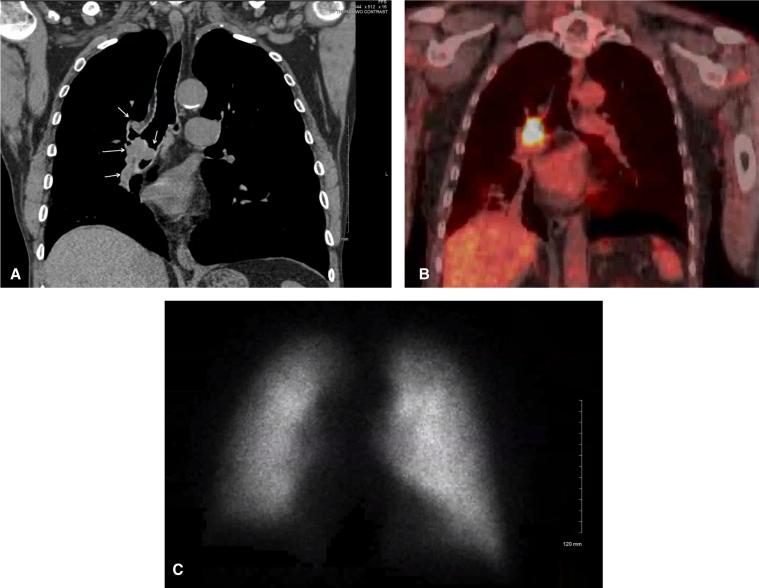

Thoracoscopic right intrapericardial pneumonectomy.